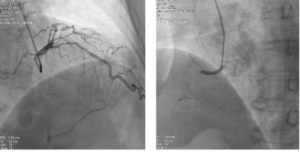

Pusat kardiovaskular dan serebrovaskular Rumah Sakit Changsha Jingkai dibangun bersama oleh klinik rawat jalan kardiovaskular dan bedah, bangsal umum, CCU, dan pusat intervensi. Diagnosis dan pengobatan...